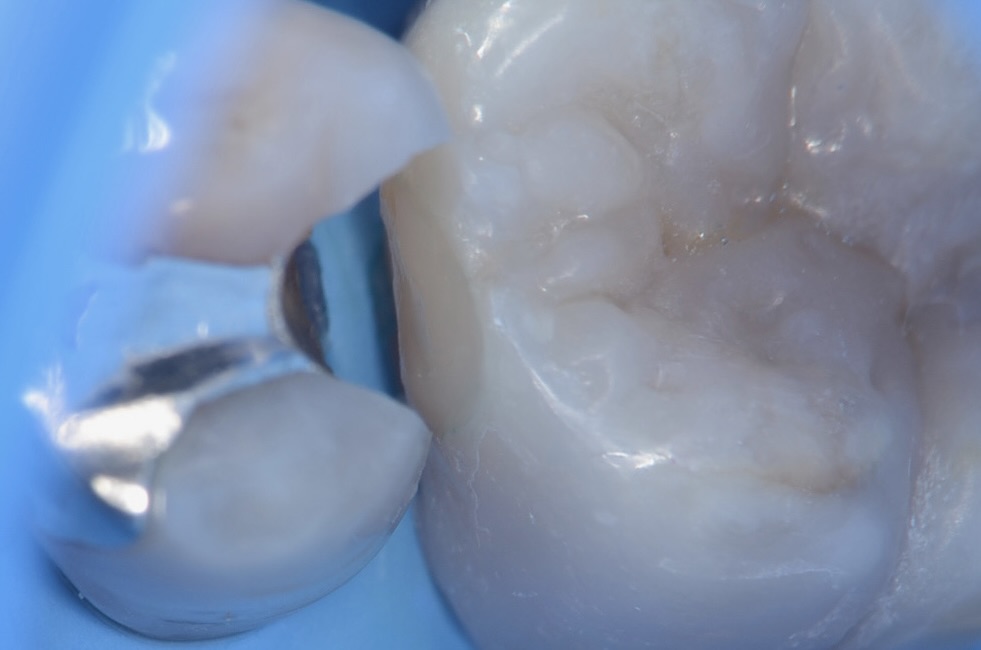

口蓋側面観

滑らかな曲線でフロスも引っかからないです。